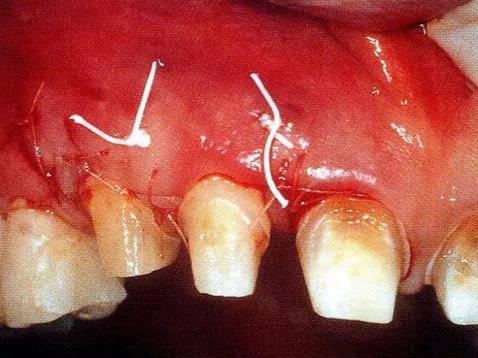

▼圖14-4 讓牙齦乳頭部緊密貼合進行縫合。

▼圖14-5 同咬合面觀。使用了Gore-tex和6-0可吸收縫合線。